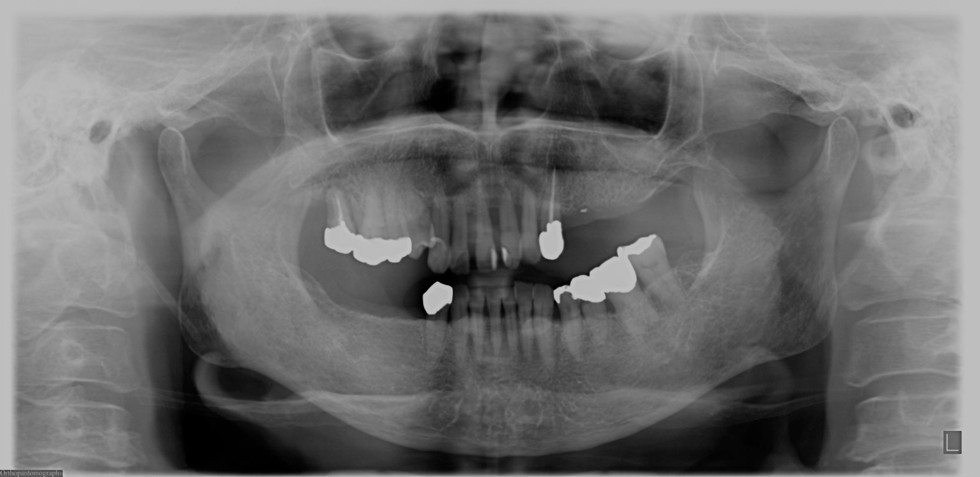

多数歯欠損のインプラント治療の症例(うえだ歯科)

上田大介(うえだ歯科)

症例詳細

| 主訴 | 歯がグラグラで噛むことができない。インプラントをして欲しい。 |

| 治療内容 | 歯周病で骨の吸収が重度で保存不能なため抜歯、仮の入れ歯を作り、6ヶ月の抜歯窩の治療の後に、インプラントのCTによる診査診断を行い、下顎に6本インプラント埋入と同時に仮歯を入れる。その後、上顎は8本のインプラント埋入と同時に仮歯を入れる。左右上6はソケットリフトによる上顎洞拳上術を行う。その後免荷期間6ヶ月待ってセラミックを用いた上部構造作製、装着しメンテナンスに移行する。 |

| 治療費 | 9,000,000円(税込) |

| 治療期間 | 2年3ヶ月 |

| 治療回数 | 90回 |

| 想定されたリスク | 重度の歯周病により無歯顎になったため、プラークコントロール不良による、術後のインプラント周囲炎が懸念される。歯冠の部分はセラミックなため欠ける可能性がある。 |